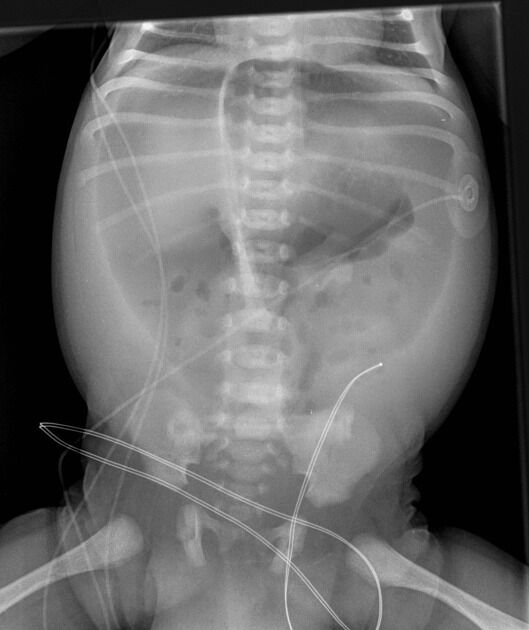

5 一位 9 個月男嬰發燒、嘔吐、腹瀉 3 天,糞便帶有血絲與黏液,至急診所做的腹部 X 光檢查如圖所 示,下列那一項處置最不適當?

Falciform ligament sign常表示肝周圍有游離空氣,這在臨床上常常提示有內臟穿孔的可能。

是下消化道鋇劑攝影檢查的禁忌症【合記2013年醫師國考試題詳解p294,295】

下消化道鋇劑攝影檢查

是針對大腸的特殊 X光檢查,包括了直腸、乙狀結腸、下結腸、橫結腸、上結腸、盲腸及闌尾,用以診斷慢性腹瀉、血便、便秘、腸躁症、無法解釋的體重減輕、排便習慣改變、貧血等。

(D)涵蓋厭氧菌and腸道內G(-)的抗生素 是可行的

附上一張較明顯的Falciform ligament sign